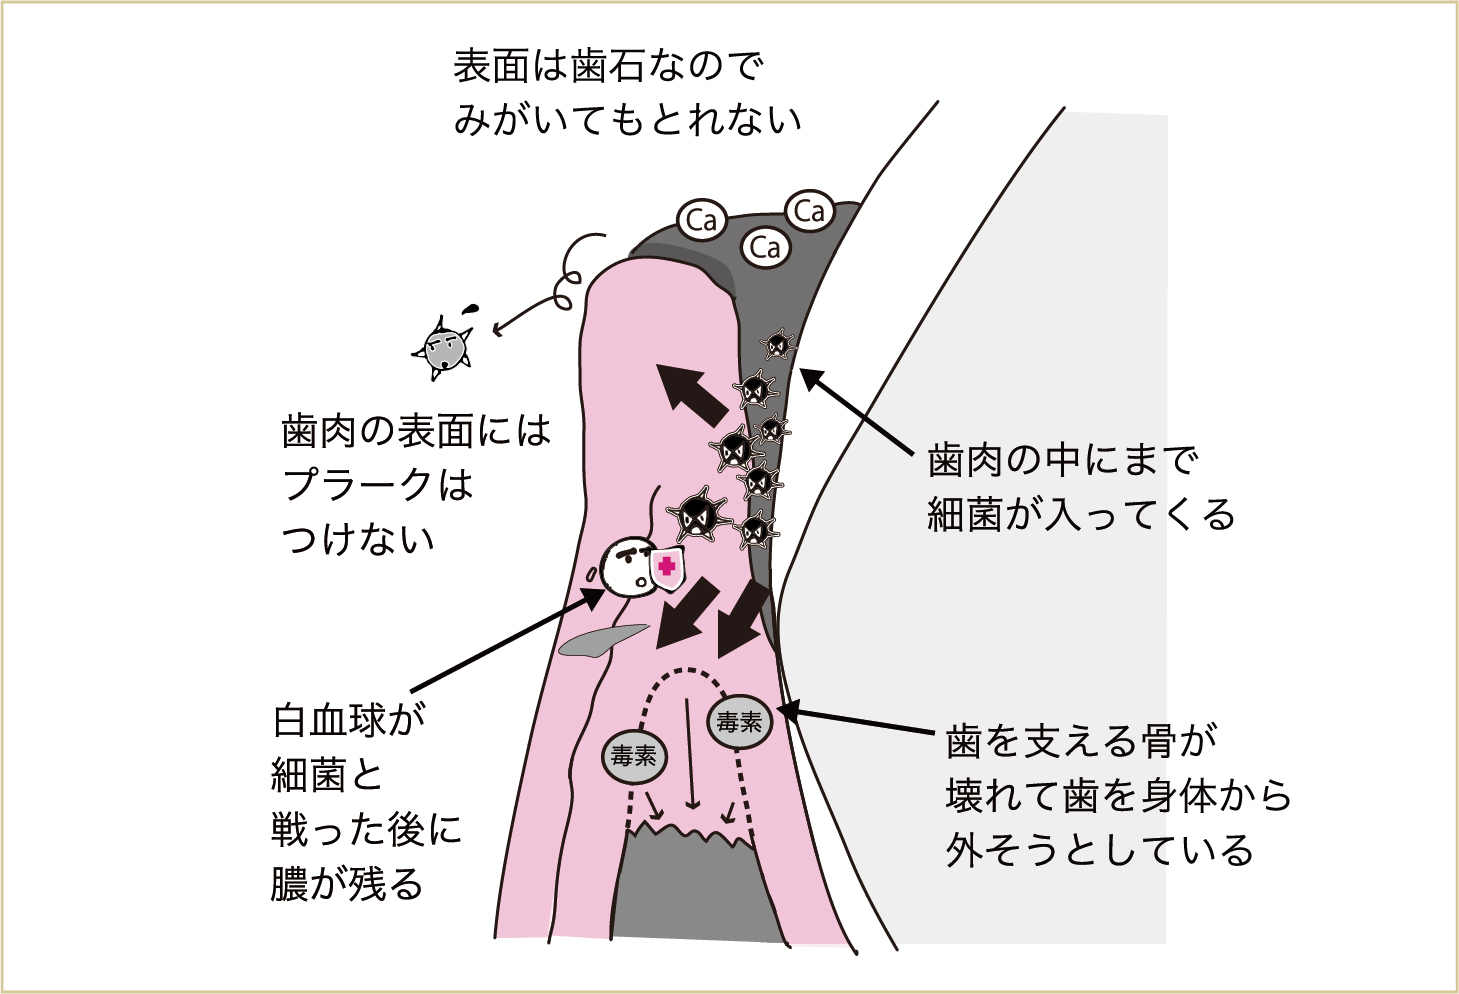

汚れが重なってくると、その表層には唾液中のカルシウムなどが沈着して硬くなっていきます。これが「歯石」で、この歯石の状態になってしまうと、歯ブラシでみがいてもとれなくなってしまいます。このような状態になる前に対処することが大切なのです。

こうしたことが何度も繰り返されると、毎日の積み重ねで、最初についた汚れの部分には空気が触れなくなってきます(口腔内は普通、空気に触れている)。そうすると、空気がない所で元気になる細菌(嫌気性細菌という)が増えてきます。この嫌気性細菌が出す汗や老廃物(毒素)は、よりいっそう、歯肉などに対して毒性が強いのです。

みがき残しが何層にも降り積もると、初めについたみがき残しは空気が触れにくい環境になり、より毒性の強い菌(歯周病原菌、嫌気性細菌)が増えてくる。

表面が歯石でガードされているため、ブラッシングしても汚れはとれない。空気が触れにくい深部には、より毒性の強い菌が増える。そのため歯肉に多くの毒素が入り込み、歯と歯肉とのバリアが壊されていく。

こうなると、歯肉が腫れる(新しいが弱々しい血管をたくさんつくって、新鮮な血流を増やす)だけでは対応できなくなってきて、今度は歯を支える骨が壊れはじめます。

つまり歯があるために、身体(血液中)に細菌が進入してくるのです。歯がなくなれば、これらの細菌がすみつく場所もなくなることを、身体はわかっています。歯のない部分の歯肉や頬には細菌はつくことができず、飲み込まれて胃液の酸で多くが死滅していきます。そこで、身体から歯を外してしまおうという反応が起こります。

この反応が歯周炎です。つまり、歯周病とは歯を支える骨が壊れることなのです。 歯を支える骨が壊れはじめると、プラークはこの壊れた部分、骨がなくなった部分にまで侵入してきます。これが繰り返されて、歯を支える骨が大きくなくなると、歯はグラグラと動揺してきます。

さらに病状が進行すると、細菌による毒素は、歯肉だけでなく、歯を支える骨や歯根表面にまで悪影響を与える。その結果として、歯を支える骨が壊れていく。